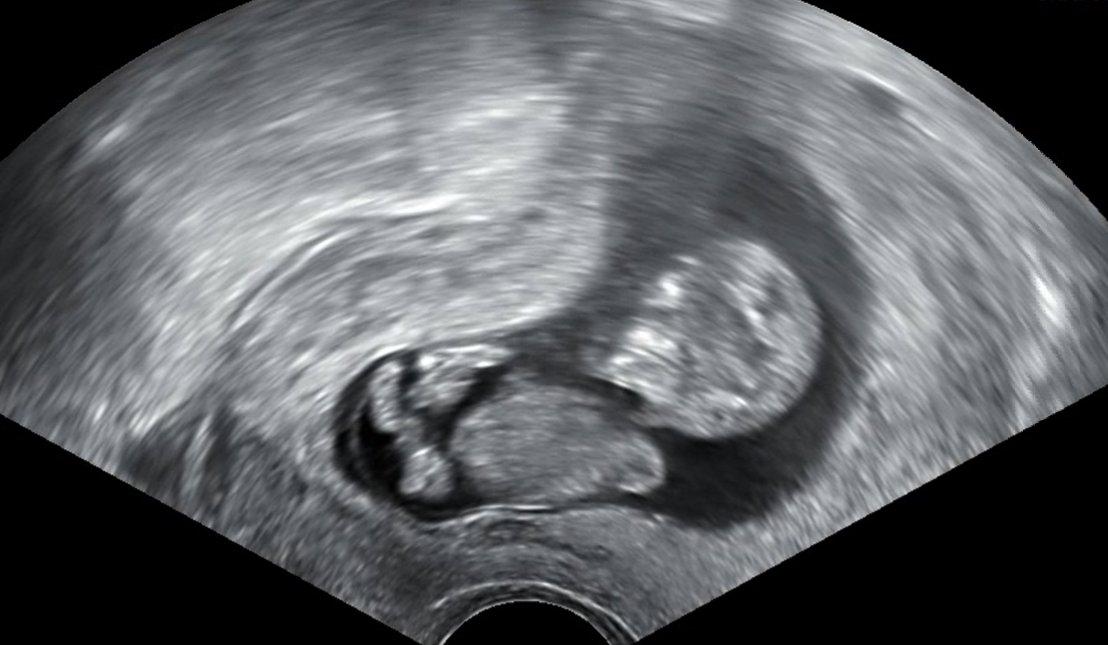

@misina01 Nene je ti moje třetí ... byla jsem v 7+3tt a viděla už srdíčko jak krásně bije..je to úžasný pocit 🌼💗💗 ... já jsem měla poslední ms 14.6. ... příští týden ve středu jdu na další kontrolu tak doufám že buď všechno v poradku a 13.9. jdu na ten screening... a co ty jak jsi na tom ? To je tvoje první ?

@misina01 No tak to je v pohodě Kočko ...úžasný pocit když to srdíčko bílo ze ? 💗 Já take dneska byla na kontrole... z 11+3tt jsem na 12+1 😍 jsem vždycky unesena jak prcka vidím ..příští týden jdu na ten screening... tak snad bude pěkně otočený a uvidíme pohlaví 😂